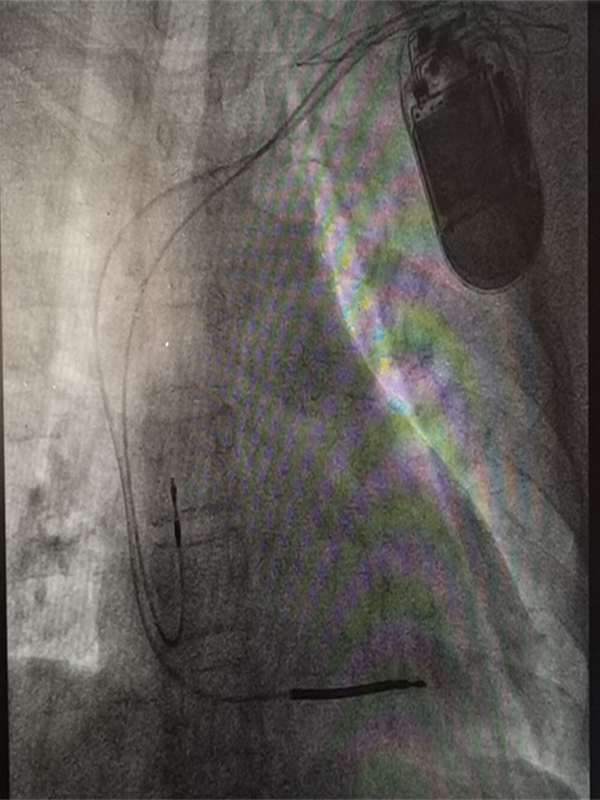

ICD 40 2

ICD

ICD ICD ICD ICD